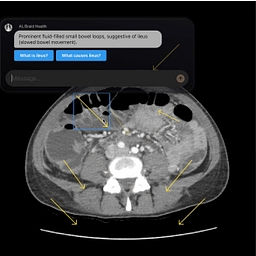

Trusted radiologists + AI insights. Fast answers, human care—right when you need it.

What they do: AI-powered diagnostic collaboration platform for radiology